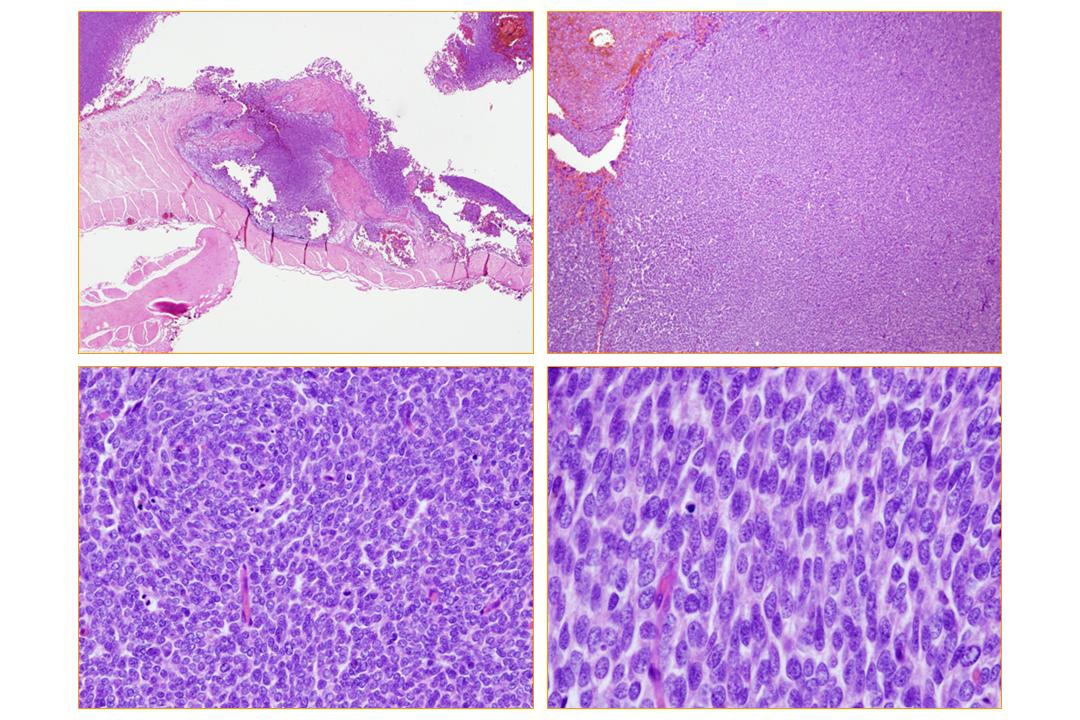

| 腫瘍は境界明瞭で,N/C比大,比較的小型で円形の細胞がびまん性,充実性に増生しており,一部腹直筋のfasciaに浸潤している.円形,類円形の細胞が主体で,一部流れる様な紡錘形の細胞が渦巻状配列に見える部分も認められる.多数の核分裂像(+). |

腫瘍細胞はCD99, CD56, bcl-2, vimentinが陽性を示した. |